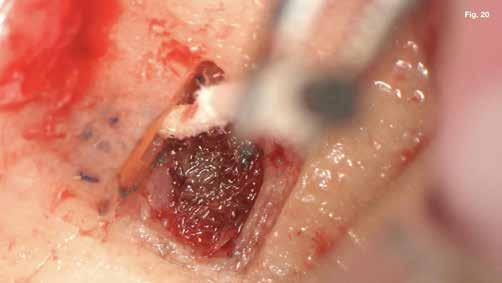

tuk. Az apikális reszekciót (8. ábra) az „UC1” (Guilin Woodpecker Medical Instrument Co., LTD) segítségével végeztük el, és a gyökeret egy 3 mm-es „MM4” (Hu-Friedy Manufacturing Co. LLC) kerek tükörrel vizsgáltuk a VRF szempontjából (13. ábra). A gyökérvég polírozását (11. ábra) az „UL4” (Guilin Woodpecker Medical Instrument Co., LTD) segítségével végeztük. A csontos kripta küretizálása kézi küretezéssel történt, de a csontos kriptában lévő további hámbélés eltávolításával a gyógyulási folyamat felgyorsítása érdekében piezo „UL3” (Guilin Woodpecker Medical Instrument Co., LTD) piezo hegyet is használtunk (9–10. ábra). A három mm-es retropreparációt (14–17. ábra) a „JT2SA” hegy (B&L Biotech) segítségével végeztük el. A retropreparációt ismét ellenőriztük a guttapercha maradványok tekintetében, leöblítettük és papírhegyekkel meg-

szárítottuk (18–20. ábra), majd retropecsétet (21–23. ábra) készítettünk „Neo Mta plus” (Avalon Biomed). A csontos blokkot visszahelyeztük (24. ábra) az eredeti helyzetébe, és a „Jason membrán” (Botiss Biomaterials GmbH) reszorbálható kollagénmembránt használtunk a blokkablak lefedésére (25. ábra). A lágyrészek varrására (26. ábra) nem felszívódó 6,0 monofilamentumos varratokat használtunk (SMI), amelyeket az 5. napon eltávolítottunk (27. ábra).